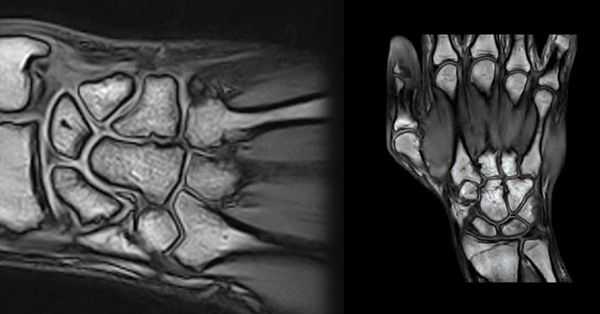

(Слева) МРТ Т2ВИ, аксиальный срез: в канале Гийона обнаруживается большой, тонкостенный ганглион неправильной формы, который сдавливает и смещает в латеральную сторону локтевой нерв.

(Справа) МРТ Т1ВИ, аксиальный срез: определяется жировое объемное образование овоидной формы, что соответствует липоме канала Гийона, окружающей нервно-сосудистый пучок в его проксимальном отделе. У пациента присутствуют симптомы слабости и парестезии в четвертом и пятом пальцах. Запястный канал без особенностей. (Слева) МРТ Т1ВИ, коронарный срез: у пациента с давней нейропатией локтевого нерва наблюдается распространенная атрофия (отмечено указателями) собственных мышц кисти. Квадратный пронатор и глубокий сгибатель пальцев без особенностей.

(Справа) МРТ Т1ВИ, аксиальный срез: у этого же пациента определяется атрофия (отмечено указателями) тыльных и ладонных межкостных мыщц и мышцы, отводящей мизинец. Червеобразные мышцы и мышцы тенара не изменены. (Слева) На рисунке коронарного среза показано аномальное мышечное брюшко поверхностного сгибателя пальцев. Это вызывает уменьшение просвета запястного канала и может привести к синдрому запястного канала вследствие компрессии срединного нерва в ограниченном пространстве.

(Справа) МРТ, протон-взвешенное изображение, аксиальный срез: у пациента с тяжелым фиброматозом определяется несколько гиперинтенсивная фиброзная ткань запястного канала и канала Гийона. У пациента нейропатия срединного и локтевого нервов.